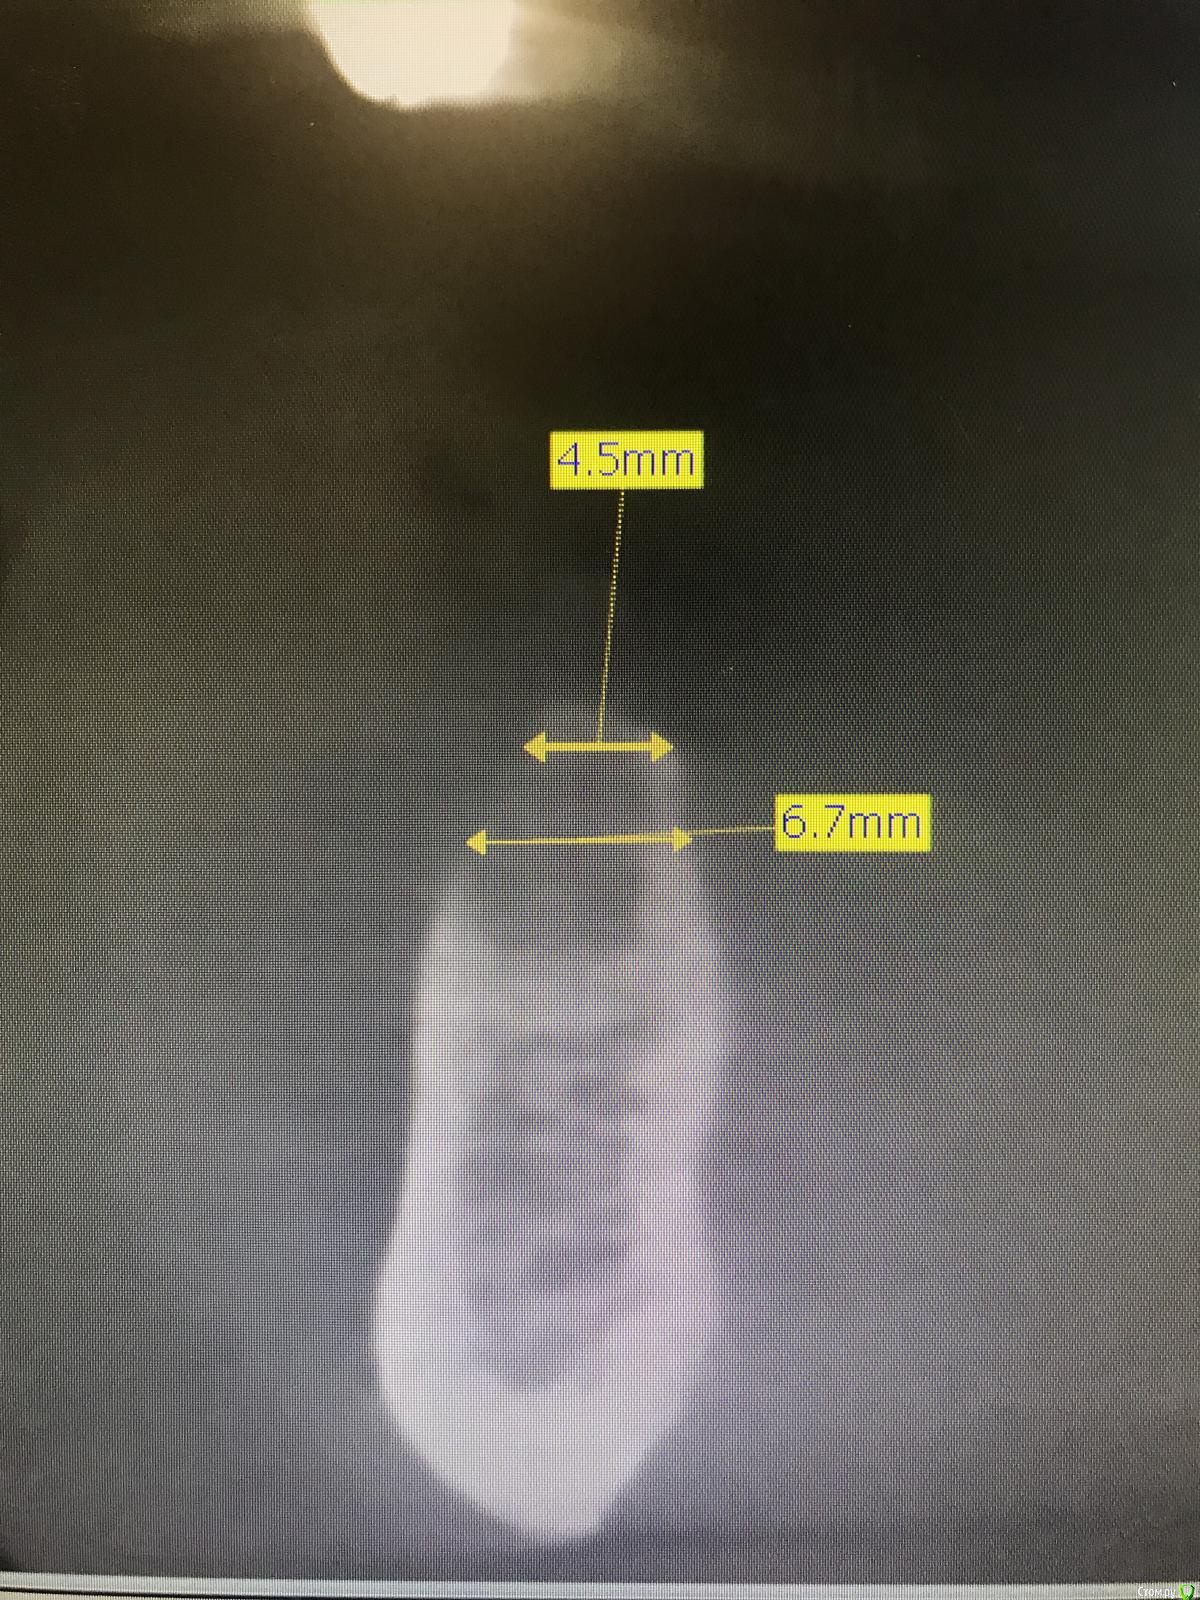

Santi Опубликовано 19 сентября, 2018 Автор Поделиться Опубликовано 19 сентября, 2018 Кт до 34, 3644,46 Ссылка на комментарий

Santi Опубликовано 21 сентября, 2018 Автор Поделиться Опубликовано 21 сентября, 2018 Как поступали с ментальным нервом в зоне аугментации?Ментальное было ниже зоны аугументации , не помешало никак) Ссылка на комментарий